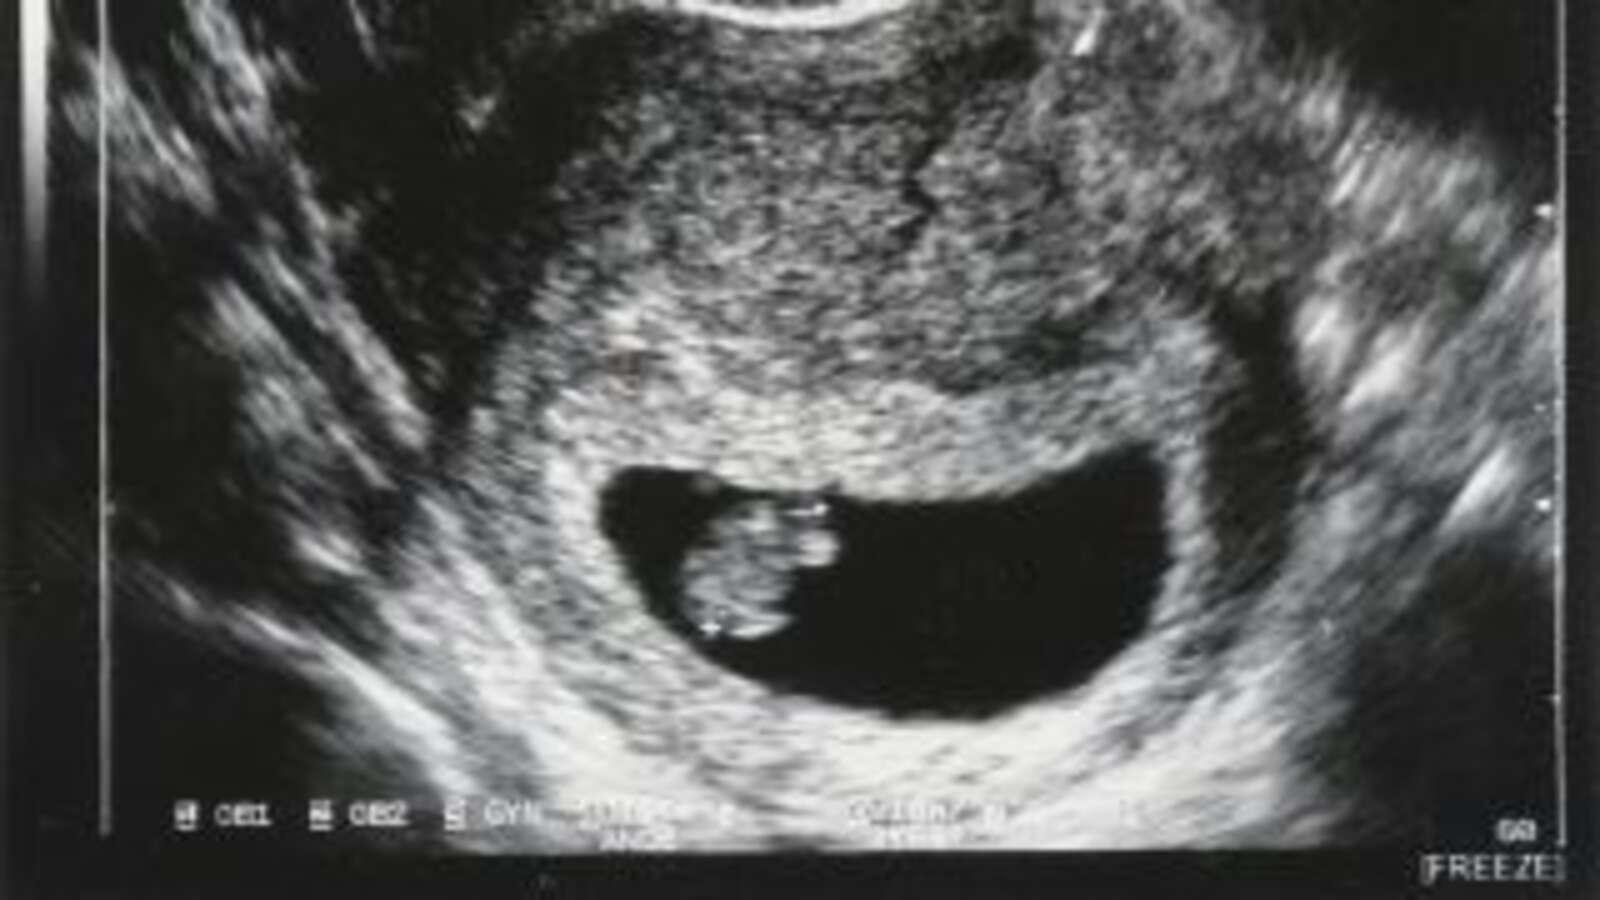

This is because gestational age (weeks of pregnancy) is not how much embryo or fetus you have in your body, but how long it has been since the first day of your last period . Let’s use the example of a woman (let’s call her Jane) with a perfect textbook cycle. She starts her period on January 1 and has sex only once in her life, resulting in a pregnancy. These dates can vary from person to person, so this is just an example:

- January 21: A developing embryo is implanted into her uterus. She is now pregnant, more precisely, in the third week of pregnancy .

Thus, the earliest thing you can know about your pregnancy is “four weeks” gestation, which means that the embryo was implanted into your uterus for only one valid week and only existed for two weeks. But the dates are counted as if the pregnancy occurred on January 1st.